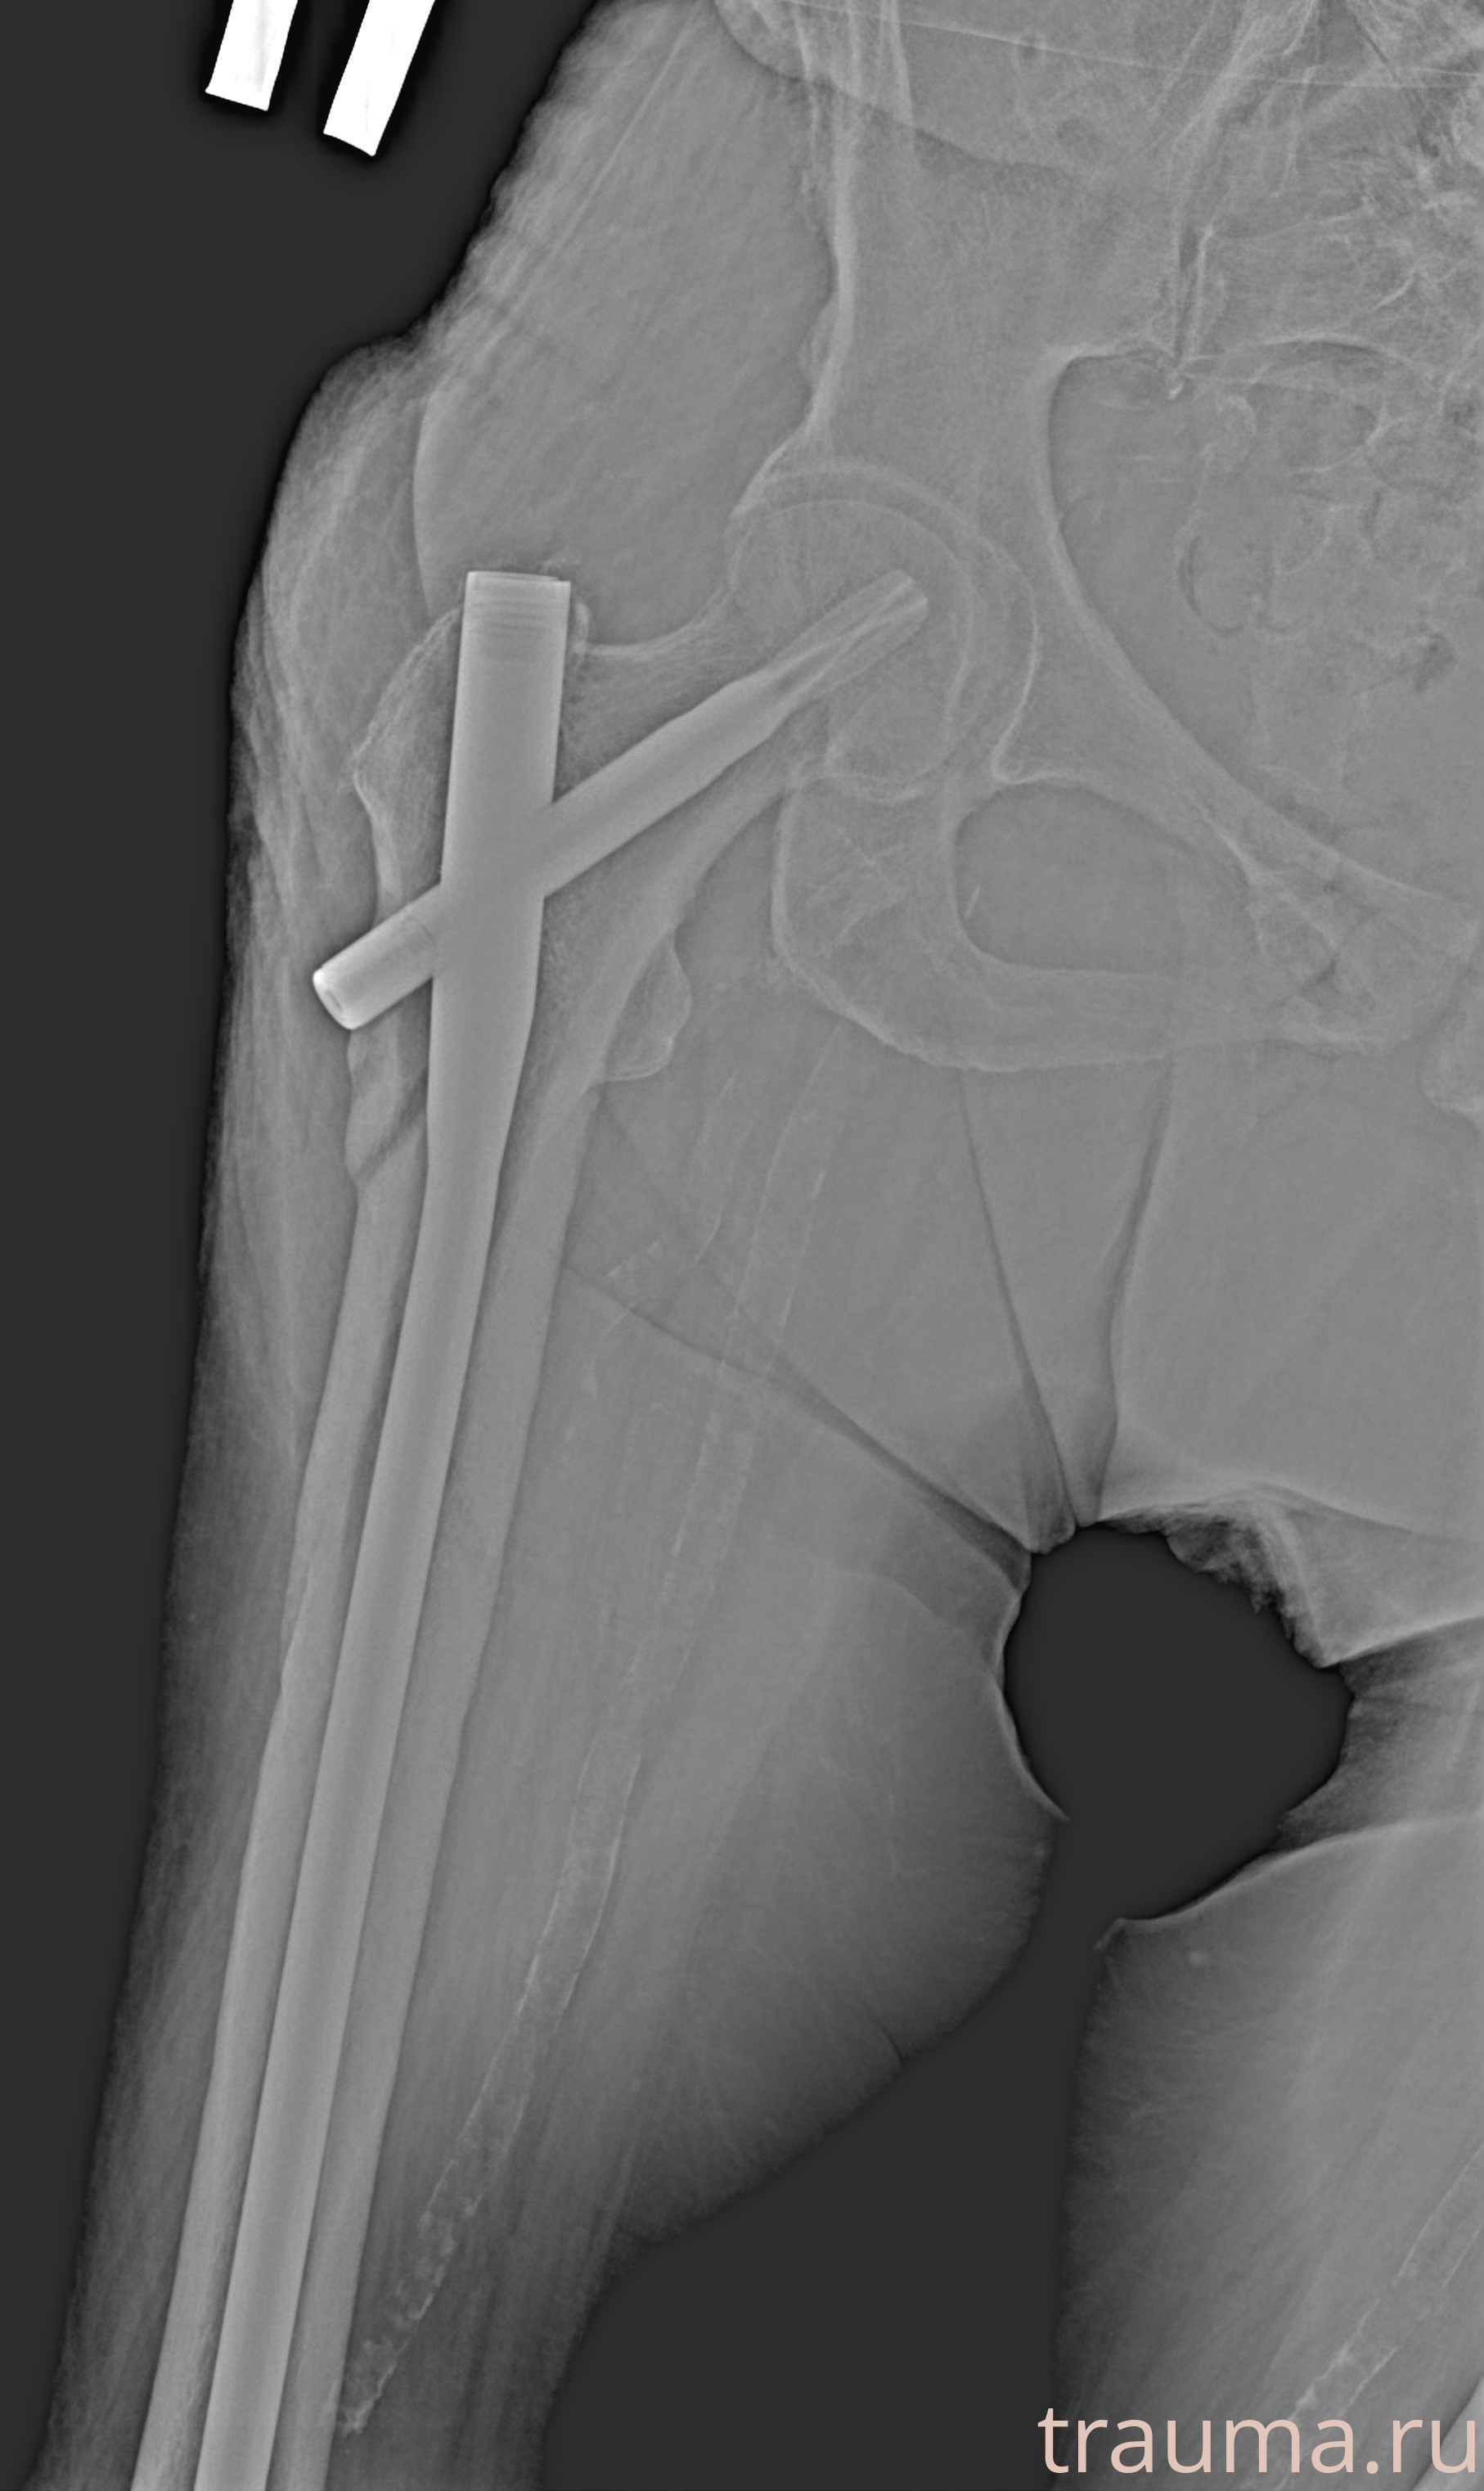

Рентгенограммы

Рентген на дому: по вашему адресу приезжает врач-рентгенолог, травматолог-ортопед с мобильным рентгеновским аппаратом, проводит диагностику травмы или заболевания, делает необходимые рентгенограммы, дает рекомендации по дальнейшему лечению. Получить качественные снимки в домашних условиях возможно благодаря уникальной методике, разработанной МосРентген Центром для института  Склифосовского